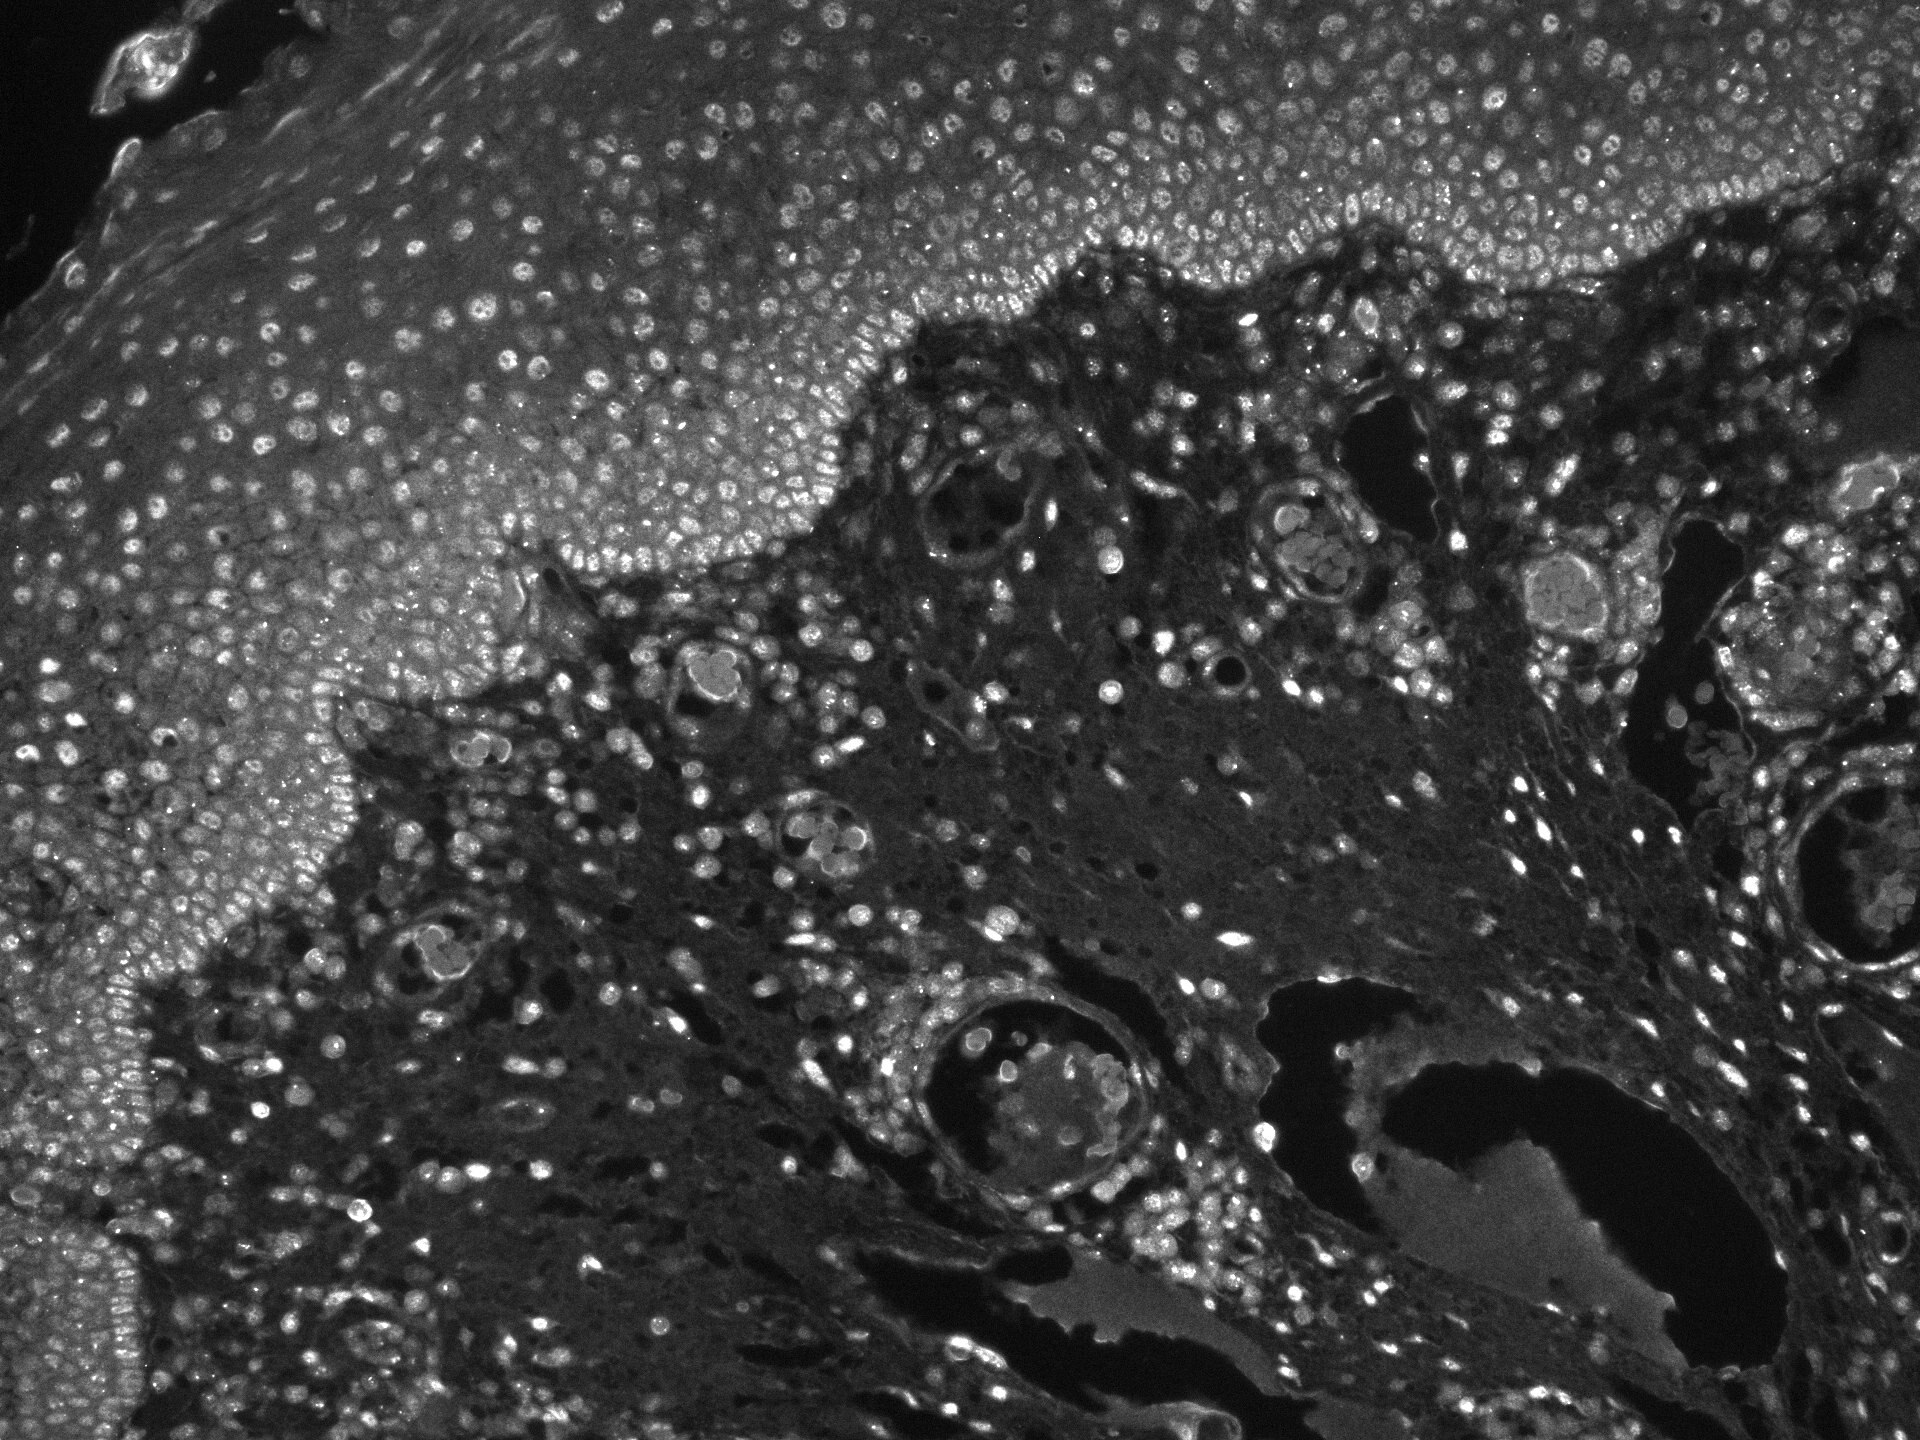

Immunohistochemistry-Paraffin 53BP1 MAB18771

IHC-P Human 04/03/2023

ApplicationImmunohistochemistry-Paraffin

Sample Testedhuman tonsil

SpeciesHuman

LotCKKF02201221